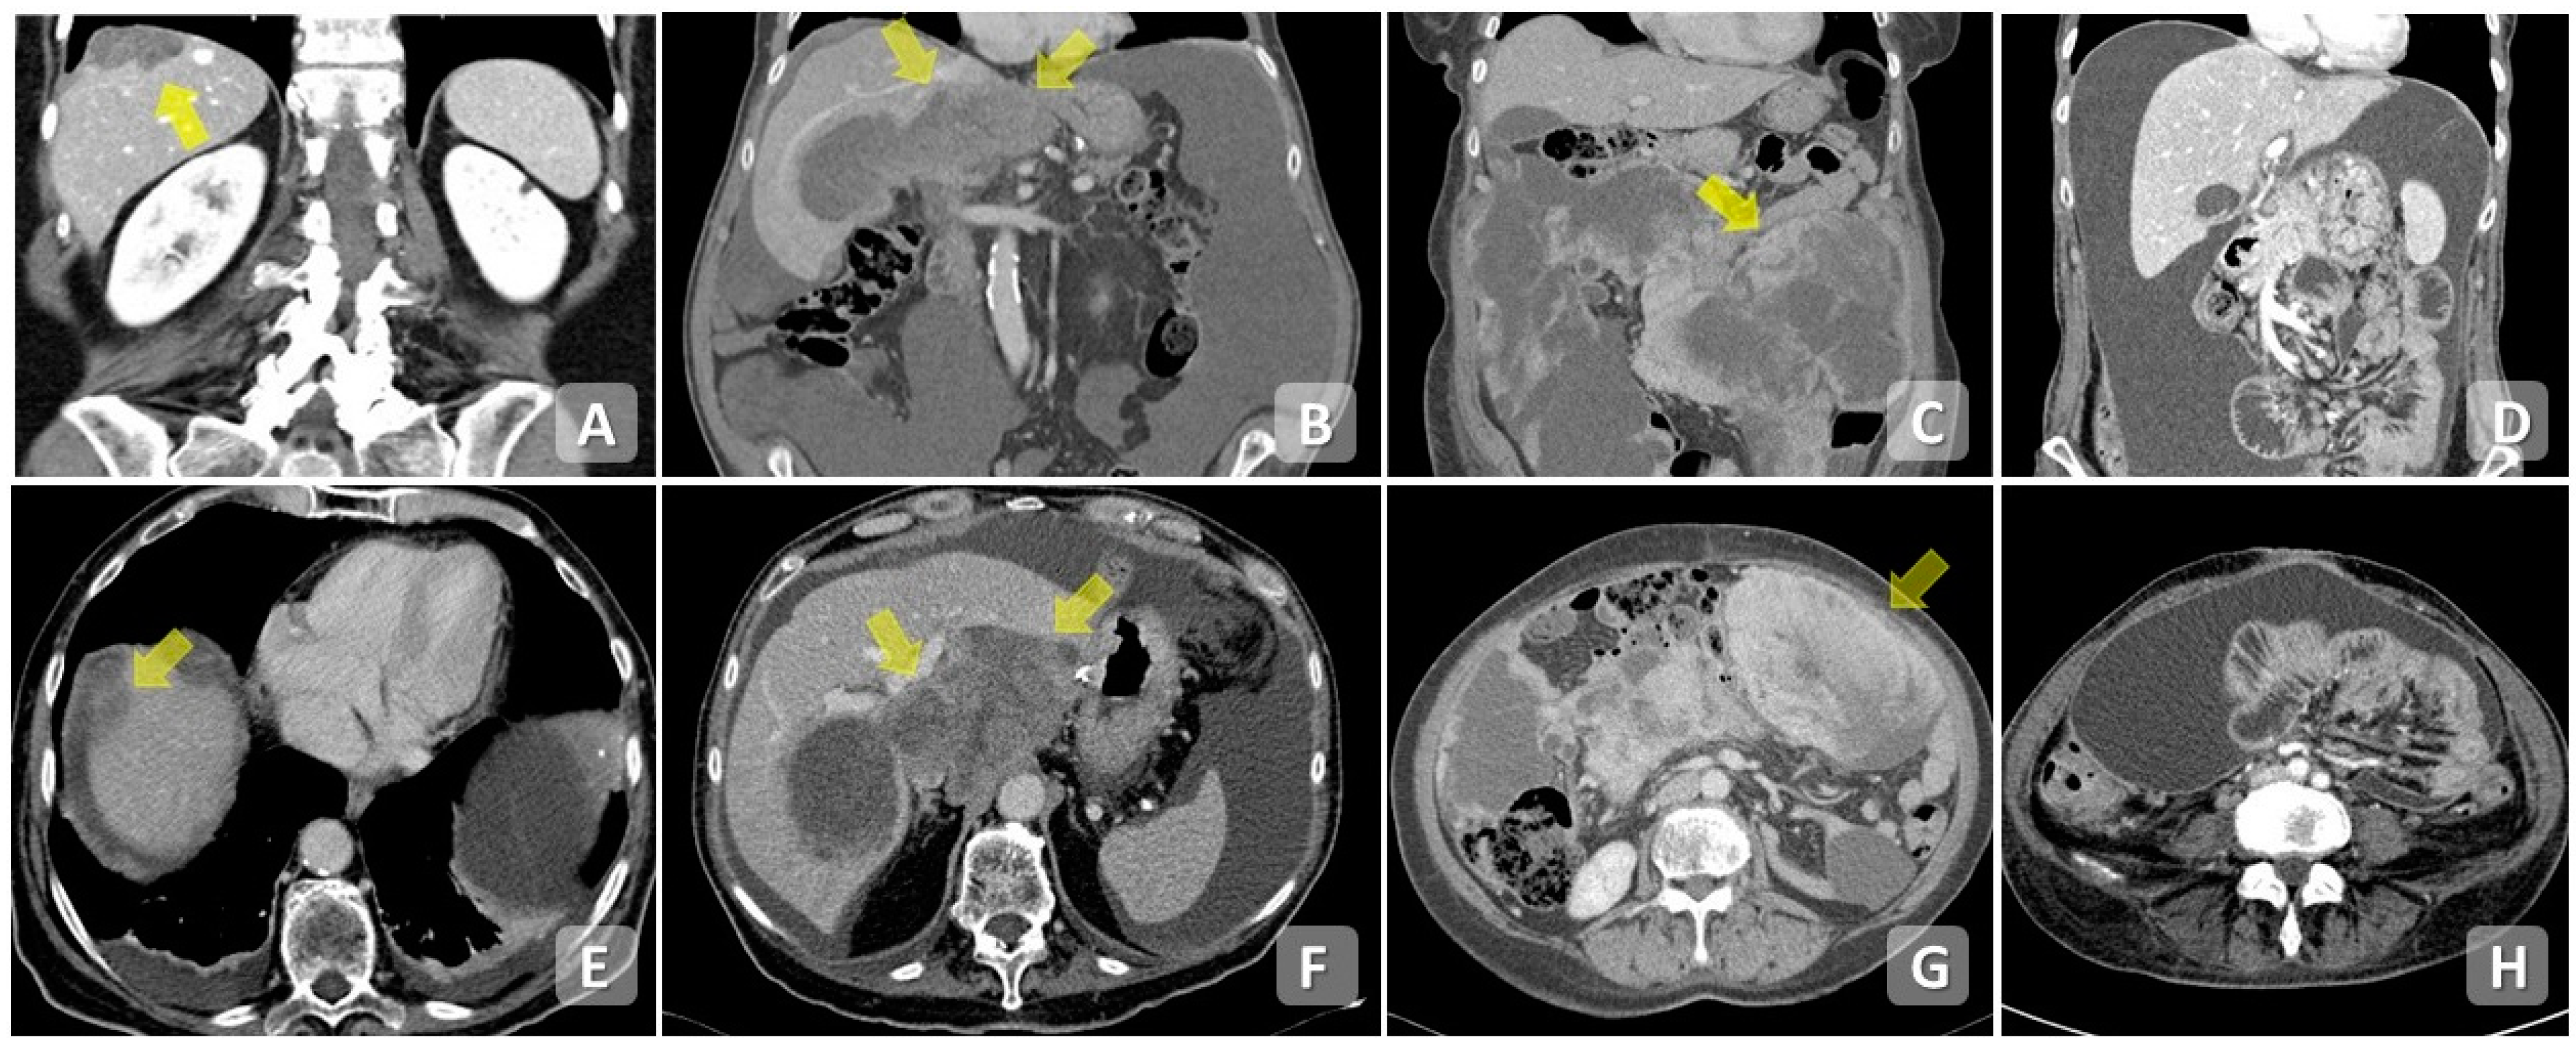

4.1. Computed Tomography

6. Disease Patterns

7. Scoring System in Diagnostic Imaging

7.1. Peritoneal Cancer Index (PCI)